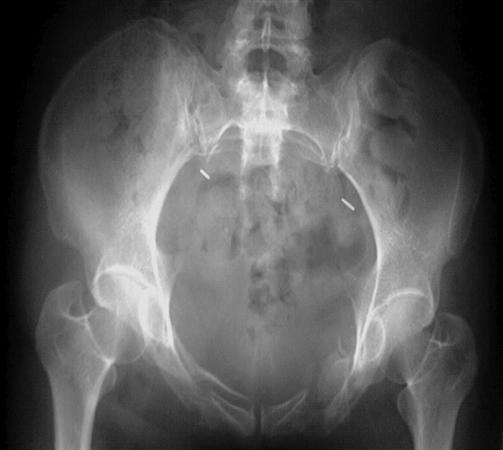

APC (AP compression)는 anterior injury로 symphysis diasthesis가 특징적입니다.

APC I : symphysis가 약간 열리고(2.5cm까지 경과관찰가능) SI jt가 정상 혹은 앞으로 약간 나오기도 합니다.

APC II : anterior SI가 앞으로 열립니다. posterior SI jt는 intact 합니다. sacrotuberous, sacrospinous lig도 손상됩니다.

APC III : SI jt 가 완벽하게 disruption 이 일어나고 이 경우 hemodynamic shock 가 동반되기 쉽습니다.